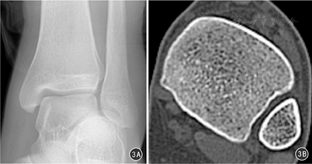

当外伤导致下胫腓联合分离后,腓骨可能会出现水平位的移位,明确外伤后腓骨在水平位是否存在移位十分重要。Prior等[9]对下胫腓联合水平,胫腓骨中心距离及胫腓骨间隙宽度进行测量研究,目的是为该病诊断找到可参照的影像学参数;但是,其研究方法存在问题,在确定胫腓骨中心时缺少必要的骨性参照点,导致研究的可重复性不佳。笔者对其研究方法加以改良,对国人的胫腓骨中心距离及胫腓骨间隙宽度进行测量研究。结果显示,半圆形与矩形下胫腓联合的胫腓骨中心距离及胫腓骨间隙宽度均存在差异。笔者认为,对于下胫腓联合为矩形切迹的患者,胫腓骨中心距离及胫腓骨间隙宽度相对较大,在踝穴位DR投影上极容易与下胫腓联合损伤的患者相混淆,但实际上其仍是正常的,这种情况下在术中是不需要固定的,如图3病例。